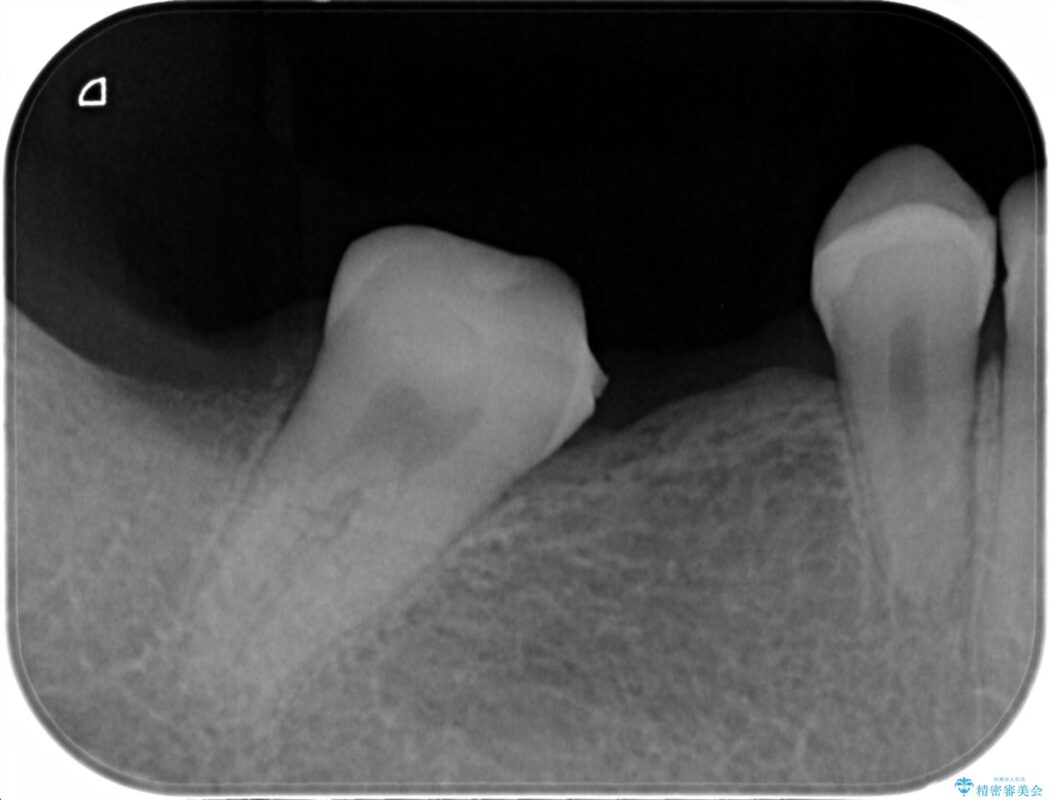

診査した結果、欠損した状態で長期間放置していたことが原因で最高峰の奥歯が欠けた部分に向かって傾斜してしまっていました。

この状態のままブリッジ治療へと進んでしまうと神経が露出する可能性が否定できないため、まずワイヤー装置による部分矯正で歯軸を通常位置へ戻してから補綴治療を行うこととしました。